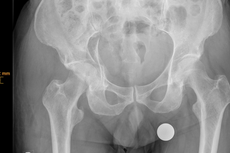

Hüftgelenksnahe Oberschenkelbrüche bezeichnen die knöchernen Verletzungen des Hüftkopfes, des Schenkelhalses oder des Rollhügelmassivs (Trochanter major und minor). In der Regel ist ein Sturz auf das Hüftgelenk oder ein direktes Anpralltrauma dafür verantwortlich. Diese Frakturen sind typische Frakturen des höheren Lebensalters.

Die Patienten werden fast ausnahmslos über die Rettungsstelle in unsere Klinik eingewiesen. Klassische Symptome sind die Gehunfähigkeit, starke Schmerzen und ein nach außen verdrehtes Bein. Lokale Blutergüsse sind häufig vorhanden.

Modernste radiologische Diagnostik steht uns zur Klassifizierung der Fraktur und der sich daraus ergebenden Therapie zur Verfügung.